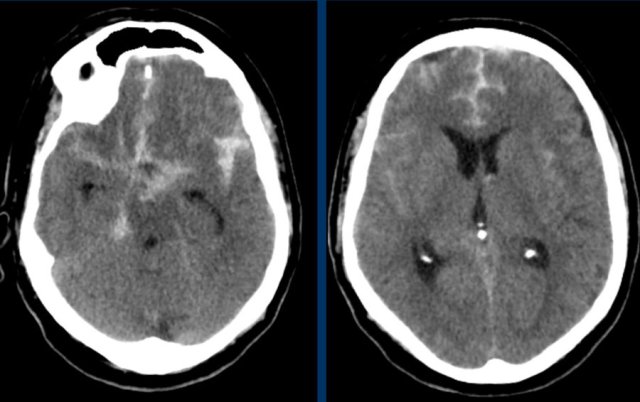

The first three images show a large hematoma in the basal ganglia on the right with massive edema.

The follow up image one year later shows  linear cavitation due to tissue loss (arrow) and hypodensity of the basal ganglia as a result of  gliosis.

The images show a hemorrhage in the basal ganglia in a patient with longstanding hypertension.

It is located in the head of the caudate nucleus.

The head of the caudate nucleus receives its blood supply from Heubner’s artery and the lenticulostriate arteries,.

A rupture in these arteries causes parenchymal hemorrhage.

The presence of an intraventricular haematoma is considered a poor prognostic factor due to the obstruction to CSF with hydrocephalus and raised intracranial pressure.